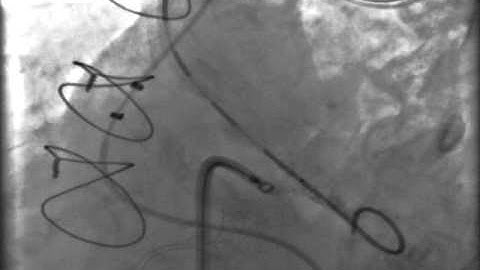

Post MI LV Pseudoaneurysm closed with ASD Device